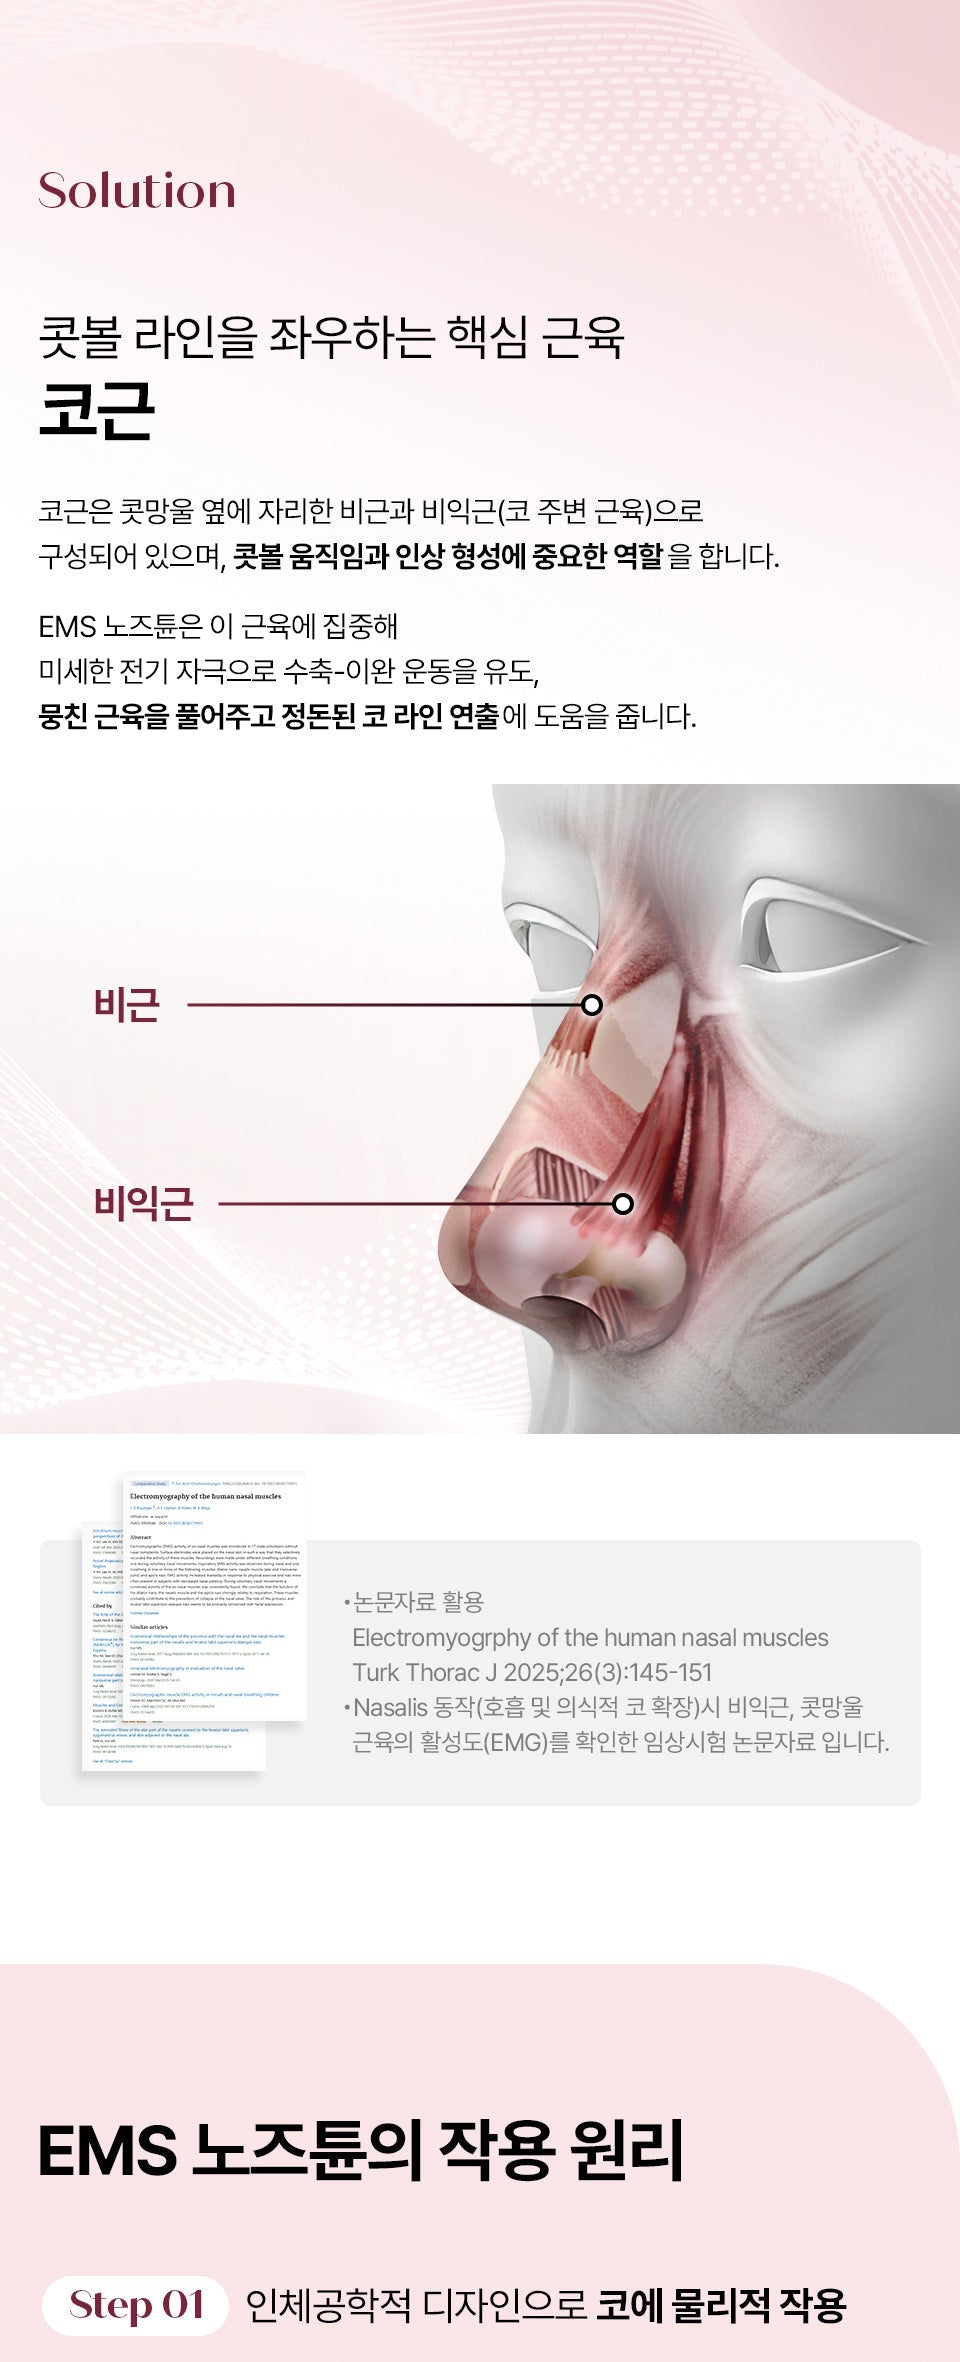

HONBODY Nose Tune is a precision beauty device engineered to sculpt and refine your nose contour effortlessly. Its compact, ergonomic design fits seamlessly into your daily skincare routine, delivering professional-grade results at home. Transform your facial appearance with this essential tool for achieving a more defined, polished look.